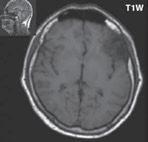

Obr. I.1.1f Rozšířené subarachnoidální prostory (věk 6 měsíců – v tomto období se nejedná o patologický stav, ale jsou fyziologicky prostornější)

Obr. I.1.1g Rozšířené subarachnoidální prostory (věk 6 měsíců – v tomto období se nejedná o patologický stav, ale jsou fyziologicky prostornější); stejný pacient jako na obr I 1 1f

f g h ch

Obr. I.1.1h Fyziologický nález, již normální šíře subarachnoidálních prostor (věk 1,5 roku); stejný pacient jako na obr I 1 1f, g

Obr. I.1.1ch Fyziologický nález, již normální šíře subarachnoidálních prostor (věk 1,5 roku); stejný pacient jako na obr I 1 1f, g, h